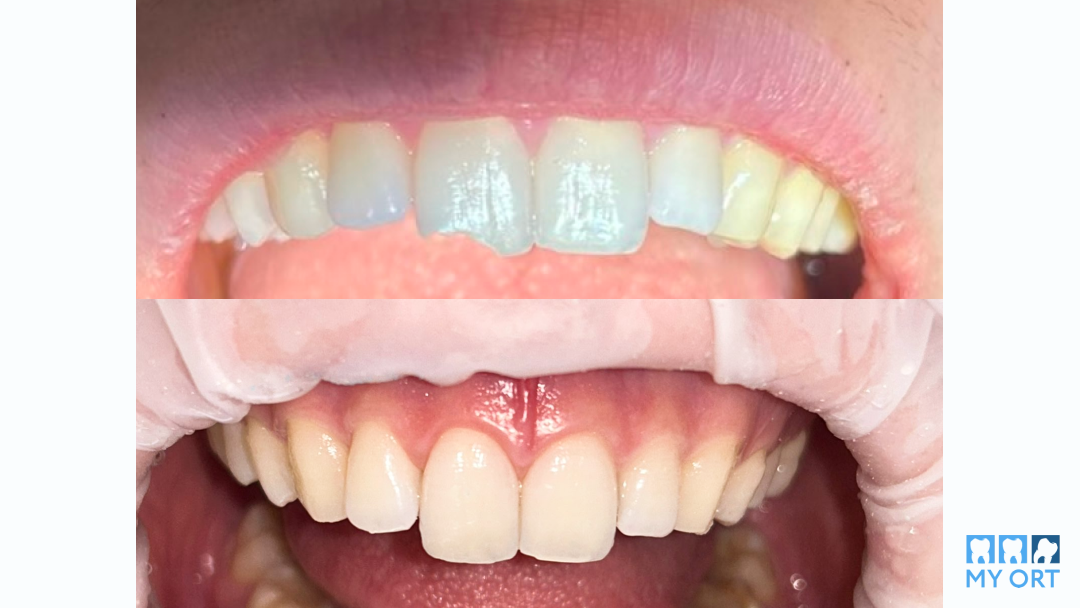

Горизонтальный перелом коронковой части зуба

Посмотрите, что у нас получилось! После реставрации зуб остался живым, стабильным, без признаков воспаления. Мы полностью восстановили анатомическую форму и эстетические свойства зуба. Цвет и текстура не отличаются от естественных зубов, функция сохранена.